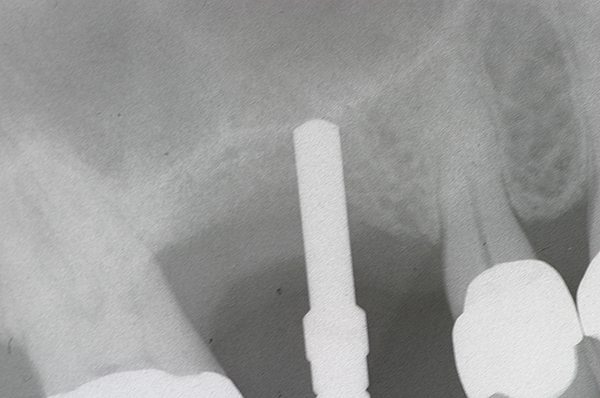

As with implant placement in general, use of a round bur is the first step in forming the osteotomy. As described above, to get verification of positioning—especially if a surgical stent is not used—a small piece of gutta percha can be placed inside this small osteotomy and a radiograph taken (Figure 1), after which the gutta percha is removed. The next step is the most critical, as it involves exposing the Schneiderian membrane. A 2-mm twist drill is used at a speed not exceeding 250 rpm, using a very light touch. Because the bone quality in the maxillary posterior is generally poor, it is usually easy to feel when the medullary bone has been breached and the dense cortical bone of the floor of the sinus has been reached. The cortical plate of the floor of the sinus should have been carefully measured with periapical radiographs presurgically, but it is usually about 1 mm in thickness. The most important and technique-sensitive part of this procedure is breaching the cortical plate of bone lining the sinus without tearing the sinus membrane. With a solid finger rest, good control, very light drilling pressure, copious irrigation, and a slow drilling speed, a slight “give” occurs once this plate of bone is breached. The full width of the twist drill should not penetrate the sinus floor; otherwise, the membrane will be torn. If it is not clear whether the membrane has been exposed, a flat-ended implant probe (Figure 2) can be used by inserting it into the osteotomy and feeling for the slight “give” or movement of the membrane. If the surgeon is not sure if the membrane is exposed, a radiographic marker can be used (Figure 3). If the membrane is significantly exposed, however, a radiographic marker should not be used, as this can inadvertently tear the membrane. The patient should also be warned not to bite down on the marker during the radiograph to avoid a membrane tear, and floss must be attached to the marker, so it can be retrieved if necessary.

Once a portion of the membrane is exposed, the osteotomy is widened to 2.8 mm with very light pressure, again not exceeding 250 rpm, stopping at the base of the osteotomy. The membrane should be verified with a blunt implant probe (eg, MT-BTI10, Implant site depth probe, MIS Implants Technologies Inc., www.mis-implants.com) (Figure 2), and a piece of collagen sponge or collagen membrane should be placed in the apical part of the osteotomy.

Fig 3. Radiographic marker placed just below the sinus.

Figure 3